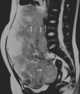

Dysgerminoma

A dysgerminoma is a type of germ cell tumor; it usually is malignant and usually occurs in the ovary. A tumor of the identical histology but not occurring in the ovary may be described by an alternate name: seminoma in the testis or germinoma in the central nervous system or other parts of the body. [Source: Wikipedia ]